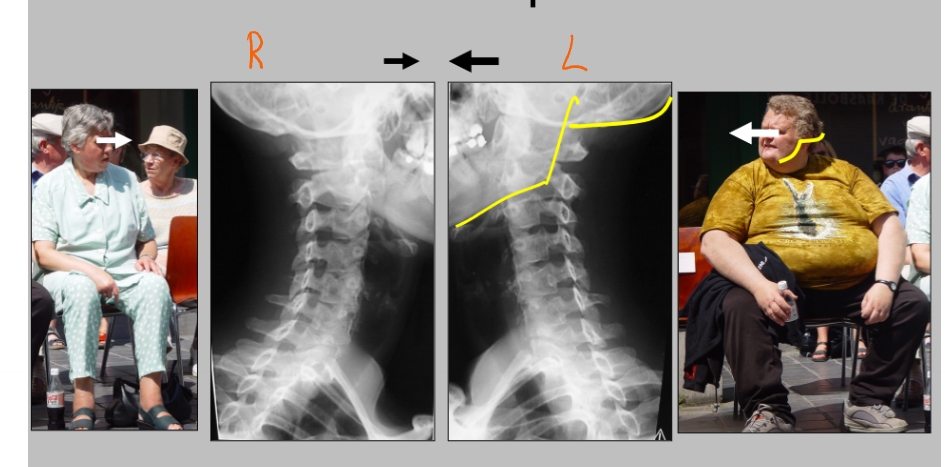

ramus mandibulae

angulus mandibulae

corpus mandibulae

formamina intervertebrale

hier komen de spinale zenuwen uit

(linker beeld → linkerkaak)

schuine opname = oblique view

foramen intervertebrale C4-C5 (links)

daaruit komt spinale zenuw C5

processus uncinatus (linker)

pedikel (linker)

spinale zenuw → gaat richting duim

= uncartrose C5-C6 (links)

klachten: cervico-brachialgie

blauwe gedeelte = osteofiet → vernauwing van foramen intervertebrale door verbening

zenuw heeft bijna geen plaats meer en wordt gekneld → last vanuit nek straalt uit naar duim

dermatoom

= uncartrose C6-C7 (links)

klachten: cervico-brachialgie

blauw gedeelte = osteofiet

pijn straalt uit naar 2e, 3e en radiale helft 4e vinger